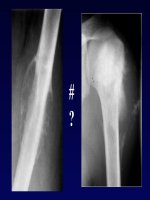

KIỂM TRA VỀ KỸ THUẬT

BÀN TAY NGƯỜI CHĂM SÓC

BỆNH NHÂN

BÓNG MỜ PHẾ NANG PHỔI (P)?

×